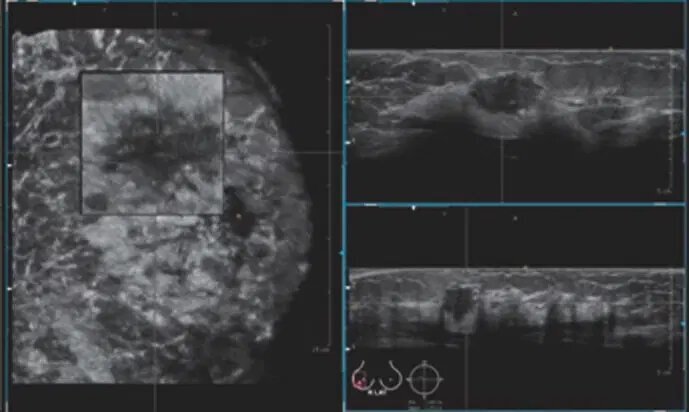

سیستم سونوگرافی بسیار پیشرفته و اسکنر حجم پستان؛ که تصاویر حجمی با وضوح بالا را از پستان به دست میآورد. این سیستم برای استفاده در زنانی با بافت متراکم پستان، امکان تجسم نمای آناتومیک کرونی پستان را فراهم میکند.